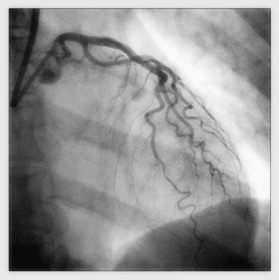

Cateterismo Cardiaco

Anatomía y extensión Choque cardiogénico No mejora con medicamentos Congestión/Edema pulmón Ventriculo derecho Inestabilidad hemodinámica o eléctrica Alto riesgo (Inhibición de glicoproteina IIb/IIIa) TIMI < 3

Caption: : http://sicimedical.com/index.php/informacion-para-pacientes/afectacion-de-las-arterias-del-corazon/que-es-un-cateterismo-cardiaco/